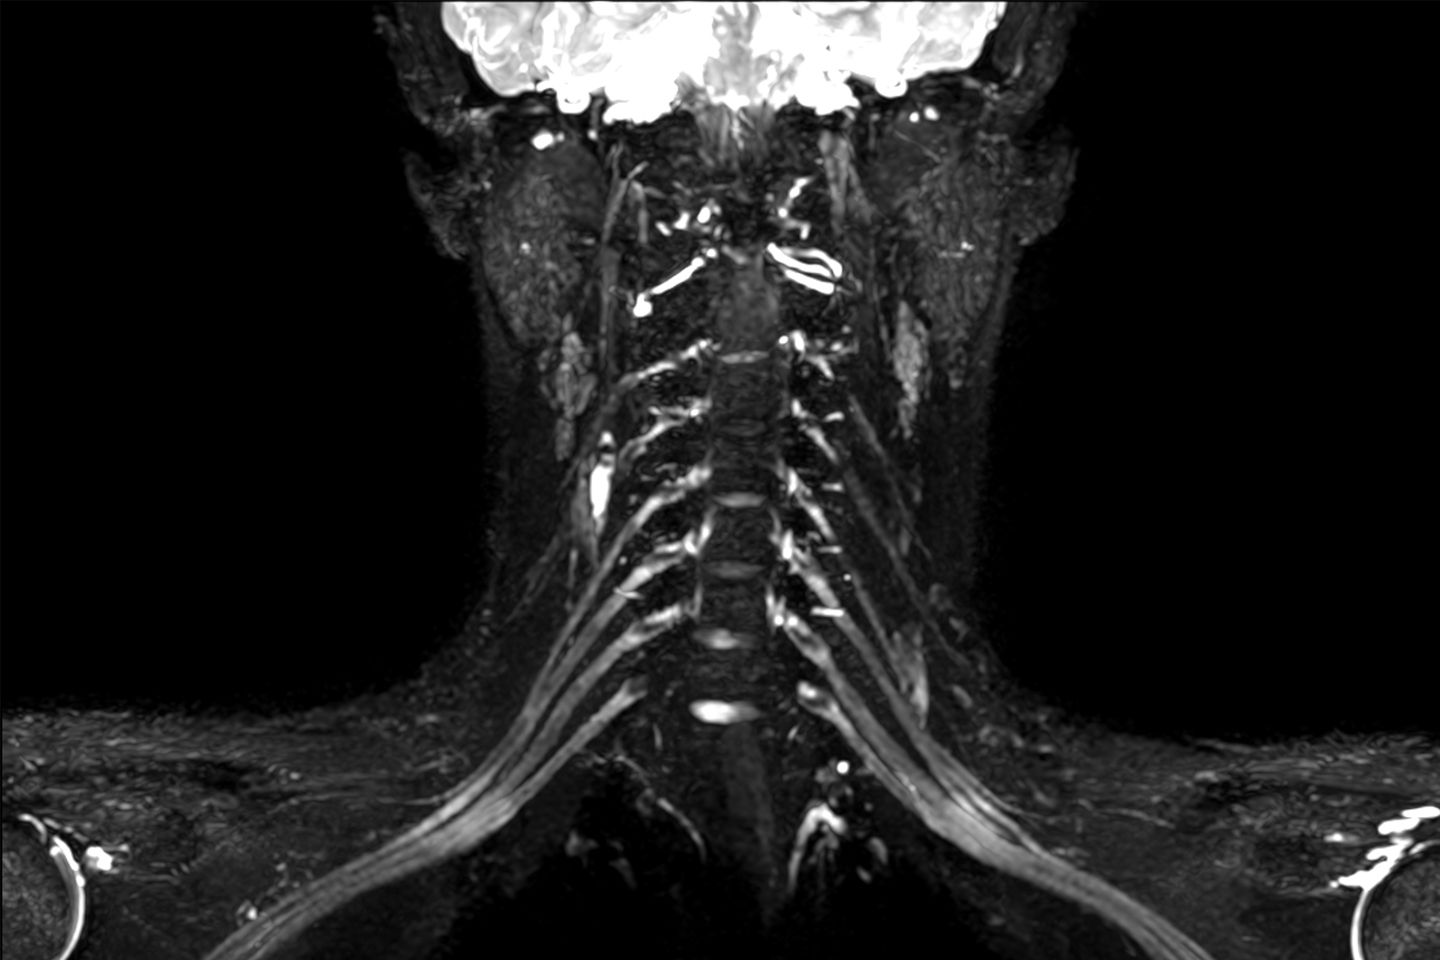

MR-Neurographie des Plexus brachialis (Nerven der Halswirbelsäule)

Wir bieten auch neuartige Verfahren zur hochauflösenden Darstellung von peripheren Nerven (sog. MR-Neurographie) an. Hierdurch können Art, Lokalisation und Ausmass von pathologischen Nervenveränderungen genau erkannt und hochaufgelöst dargestellt werden. Die MR-Neurographie bietet somit einen wertvollen Beitrag zu interdisziplinären Behandlungskonzepten von Patientinnen und Patienten mit Erkrankungen des peripheren Nervensystems.